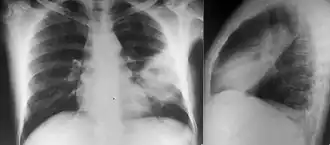

Chest X-ray showing opacity of the left middle and lower areas of the lung.[6]

Diabetes mellitus is one of the most important risk factors in developing melioidosis. The disease should be considered in anyone who has spent time in endemic areas who develops a fever, pneumonia, or abscesses in their liver, spleen, prostate, or parotid gland.[1] The clinical manifestation of the disease can range from simple skin changes such as abscesses or ulcerations to severe organ problems.[8] The commonest organs affected are the liver, spleen, lungs, prostate, and kidneys. Among the most common features are bacteremia (in 40 to 60% of cases), pneumonia (50%), and septic shock (20%).[1][9] People with only pneumonia may have a prominent cough with sputum and shortness of breath. However, those with septic shock together with pneumonia may have minimal coughing.[2] Results of a chest X-ray can range from diffuse nodular infiltrates in those with septic shock to progressive consolidation located most commonly in the upper lobes for those with pneumonia only. Pleural effusion and empyema are more common for melioidosis affecting the lower lobes of the lungs.[2] In 10% of cases, people develop secondary pneumonia caused by other bacteria after the primary infection.[3] In northern Australia, 60% of the infected children presented with only skin lesions, while 20% presented with pneumonia.[3]

Various imaging modalities can also help with the diagnosis of melioidosis. In acute melioidosis with the spreading of the bacteria through the bloodstream, the chest X-ray shows multifocal nodular lesions. It may also show merging nodules or cavitations. For those with acute melioidosis without the spread to the bloodstream, chest X-ray most commonly shows upper lobe consolidation or cavitations.[10] In chronic melioidosis, the slow progression of upper lobe consolidation of the lungs resembles tuberculosis.[10] For abscesses located in other parts of the body apart from the lungs, especially in the liver and spleen, CT scan has higher sensitivity when compared with an ultrasound scan. In liver and splenic abscesses, an ultrasound scan shows "target-like" lesions while a CT scan shows "honeycomb sign" (abscess with loculations separated by thin septa) in liver abscesses.[10] For melioidosis involving the brain, MRI has higher sensitivity than a CT scan in diagnosing the lesion. MRI shows ring-enhancing lesions for brain melioidosis.[10]